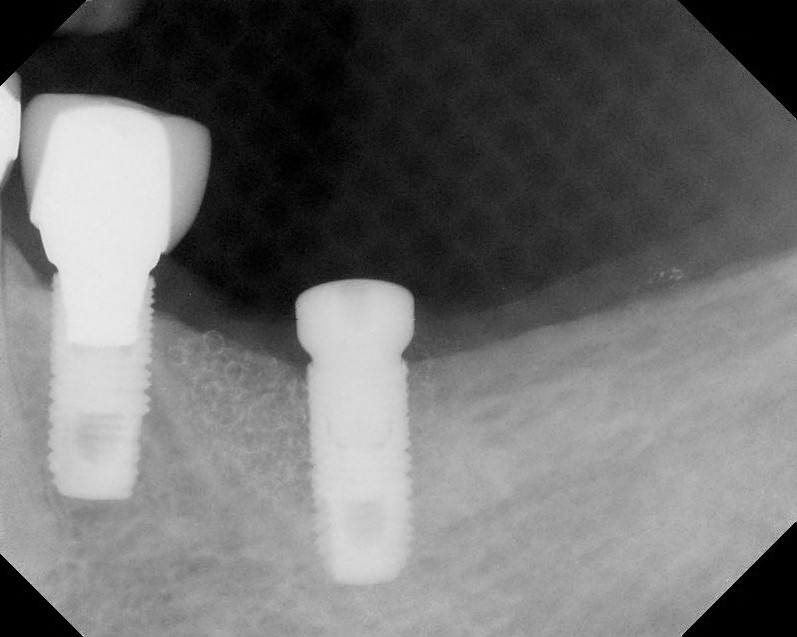

Implants

This treatment involves implanting artificial dental roots, and restoring dental crown without damaging the adjacent teeth.